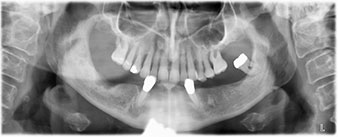

La patiente âgée de 64 ans présente une denture résiduelle des dents 38, 33 et 43 et une prothèse amovible mandibulaire stabilisée par crochets (Fig. 1 et 2).